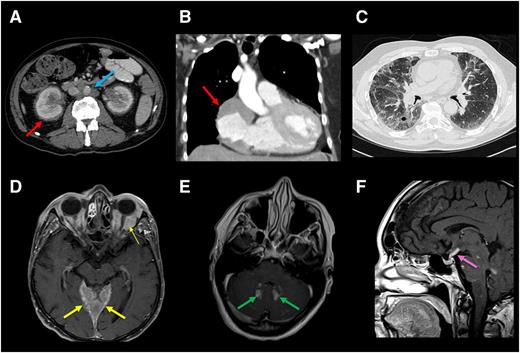

In addition to histological features, the radiographic finding of symmetric diaphyseal and metaphyseal osteosclerosis in the legs is nearly always present in ECD (Figure 1A-D). This is best visualized by radiotracer uptake in the distal ends of the femurs and the proximal and distal tibia by bone scan, and less sensitively by positron emission tomography (PET). Bone lesions may be visualized on computed tomography (CT) or magnetic resonance imaging (MRI) but are often missed on plain films.22,23 Approximately 4% of ECD patients lack radiographic findings of osteosclerosis of the femurs.15 In these cases, the diagnosis of ECD is based on histopathology and other classic organ involvement. Second, dense infiltration of perinephric fat, described as a “hairy kidney” based on its appearance on CT, is a highly prevalent (68% of cases) and iconic radiographic finding (Figure 2A).22 Even in circumstances with highly suggestive clinical and imaging features, biopsy is necessary to confirm the diagnosis and establish BRAF mutational status (Grade 2C).

Radiographic findings of internal organ systems commonly affected by ECD. (A) Axial CT scan of abdomen of an ECD patient demonstrating dense infiltration of perinephric fat commonly seen in ECD and referred to as a “hairy kidney” appearance (red arrow). Circumferential soft-tissue sheathing of the thoracic aorta seen in a subset of ECD patients and referred to as a “coated aorta” (blue arrow). Right atrial mass is demonstrated in B. (C) Lung parenchymal infiltration on chest CT in an ECD patient. Axial postgadolinium T1 MRI in (D) demonstrates expansile enhancement of the pachymeninges (thick arrow) as well as orbital masses (thin arrow) and (E) enhancing lesions in the dentate nuclei of the cerebellum. (F) Sagittal postgadolinium T1 MRI shows thickening and enhancement of the pituitary stalk.

Cardiovascular involvement is common but frequently asymptomatic and detected incidentally by CT or MRI.34,35 The most common abnormality is circumferential soft-tissue sheathing of the thoracic and abdominal aorta and its branches visualized on CT scan, the so-called “coated aorta,” present in up to two-thirds of patients (Figure 2A).15,36 If renal arteries are involved, renovascular hypertension may develop and ultimately require stenting. Coronary arterial disease resulting in myocardial infarction has been described.36-38 Pericardial disease occurs in 40% to 45% of patients and can present with pericarditis, effusion, and even tamponade.32,39,40 Mural pseudo-tumoral infiltration of the right atrium is present in up to one-third of patients, visualized clearly on MRI as a mass lesion (Figure 2B), rarely causing valvular dysfunction and conduction abnormalities.34,35 Diffuse infiltration of the myocardium or interatrial septum has been described, occasionally leading to heart failure.41,42 Involvement of intrahepatic veins causing portal hypertension as well as the mesenteric vessels leading to ischemia have been seen but not published.

Radiographic lung involvement may be present in up to one-half of cases, involving either the lung parenchyma or the pleura (Figure 2C).15,43 Plain films are typically normal, but high-resolution CT may demonstrate interlobular septal thickening, ground-glass opacities, or centrilobular opacities.22 Frank consolidations are uncommon. Fluid from bronchoalveolar lavage, if performed, may contain macrophages and foamy histiocytes. Pulmonary involvement is often asymptomatic but can rarely manifest as cough or dyspnea. Spirometry may demonstrate restrictive features and decreased diffusion capacity.

The frequency of central nervous system (CNS) involvement in ECD varies from 25% to 50%.22,44 Parenchymal CNS lesions are a significant cause of functional disability in ECD and have been found in one series to be an independent predictor of death.45 Infiltrations can occur throughout the neuraxis, both in the intra-axial and extra-axial compartments. Expansile, gadolinium-enhancing lesions of the pachymeninges can occur overlying the cerebral hemispheres or in the cerebellar tentorium (Figure 2D). They can appear similar to meningiomas, granulomatous diseases, or meningeal infiltration by Rosai-Dorfman disease or LCH.32,33 Lesions present with focal symptoms referable to compression of local structures or, when disease is diffuse and bulky, with generalized deterioration of cognition and gait. Intra-axially, ECD manifests more commonly in the dentate nuclei of the cerebellum or in the pons, causing progressive cerebellar symptoms such as ataxia and dysarthria as well as brainstem symptoms (Figure 2E).22,25,46 These abnormalities tend to be gadolinium-enhancing and may be mistaken for primary or metastatic tumors, demyelinating disease, inflammatory processes, or leukodystrophies.28,29 Similar intracranial lesions have been reported in JXG.47 Infiltrative CNS lesions in LCH have similar distribution and radiographic appearances to lesions in ECD, with the exception of meningeal lesions, which are more expansile in ECD, and the spinal cord, which is spared in LCH. A degenerative atrophic process in the posterior fossa is an uncommon but well-described manifestation of LCH48 ; neurodegenerative phenomena in ECD remain uncharacterized.

Unilateral or bilateral infiltration of the orbits occurs in ∼25% of patients and can present as exophthalmos, retro-orbital pain, oculomotor palsies, or blindness.15,49 These pseudotumoral lesions have a differential diagnosis that includes Graves disease, granulomatous disease, lymphoma, and giant cell arteritis.

Diabetes insipidus is a shared feature of ECD and LCH, occurring in ∼25% of ECD patients, although several endocrinopathies have been reported, including hyperprolactinemia, gonadotropin insufficiency, and hypotestosteronism.15 Radiographically, the pituitary gland, stalk, and hypothalamus may be normal; alternatively, enlargement and abnormal enhancement of these structures can be appreciated on MRI with or without accompanying endocrinopathy (Figure 2F).50

Infiltration of perinephric tissues leading to the “hairy kidney” is common, as is hydronephrosis and ureteral narrowing (Figure 2A). Furthermore, ∼30% ECD patients present with imaging features suggestive of retroperitoneal fibrosis; however, unlike idiopathic retroperitoneal fibrosis, the pelvic ureters and inferior vena cavae are typically spared.15 Ureteral stenting or even nephrostomy may be required if hydronephrosis is associated with renal insufficiency.